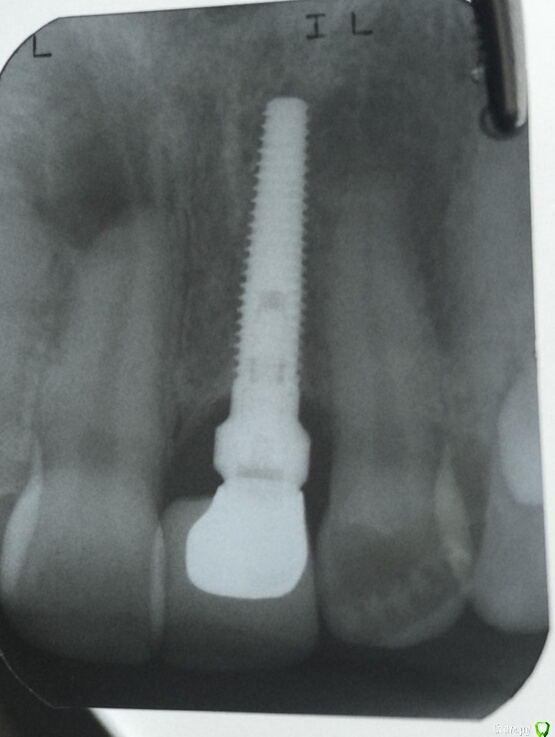

DoktorDre Опубликовано 6 января, 2016 Поделиться Опубликовано 6 января, 2016 Здравствуйте, коллеги! С наступающим Рождеством! Вопрос, подкупающий своей новизной :Что это за имплант?У коронки огромное поднутрение.грануляции. Возможно ли переделать? Непонятный абатмент... Ссылка на комментарий

doca Опубликовано 6 января, 2016 Поделиться Опубликовано 6 января, 2016 похож на Нобель 3,5Х16 Ссылка на комментарий

DoktorDre Опубликовано 6 января, 2016 Автор Поделиться Опубликовано 6 января, 2016 То есть этот набалдашник на импланте это нобелевский абатмент, и можно оставить как есть, переделав коронку? Ссылка на комментарий

doca Опубликовано 6 января, 2016 Поделиться Опубликовано 6 января, 2016 То есть этот набалдашник на импланте это нобелевский абатмент, и можно оставить как есть, переделав коронку?а это вы узнаете когда выкрутите Ссылка на комментарий

red_butler Опубликовано 6 января, 2016 Поделиться Опубликовано 6 января, 2016 Нобель или его клон Ссылка на комментарий

brg Опубликовано 7 января, 2016 Поделиться Опубликовано 7 января, 2016 Нобель или его клонИли клон его клона Ссылка на комментарий